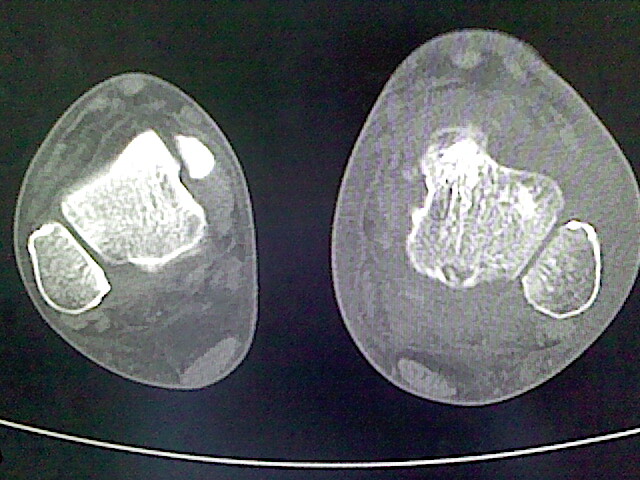

标题: CT16814:男,76岁,左小腿疼痛,不能站立 大家给看看 [打印本页]

男,76岁,左小腿疼痛,不能站立

本例骨质改变主要表现为滑膜或韧带区的骨侵蚀融解(胫腓联合区骨质破坏无硬化边),距骨后部骨质破坏区有硬化边及死骨样改变.所以,本例考虑关节结核可能性大,绒毛膜结节性滑膜炎多发于中年,且极少见于膝髋以外的关节,骨质硬坏也以压陷吸收为主,有明显的硬化边,骨膜增生呈结节状(可以mr鉴别),所以本例暂除外.

另不除外可引起相似表现的其他炎症如布氏杆菌性关节炎等